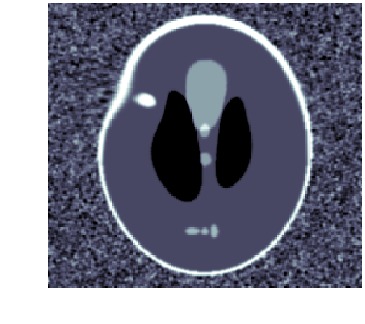

When template has correct topology and intensity levels, then \acLDDMM-based indirect registration with geometric group action is remarkably stable as shown in [9]. Using a geometric group action, however, makes it impossible to create or remove intensity, e.g., it is not possible to start out from a template with a single isolated structure and deform it to a image with two isolated structures. This severely limits the usefulness of \acLDDMM-based indirect registration, e.g., spatiotemporal images (moves) are likely to involve changes in both geometry (objects appear or disappear) and intensity. See fig. 1 for an example of how wrong intensity influences the registration.

We clearly see that metamorphosis based indirect registration can handle a template with wrong intensities. As a comparison, see fig. 1(c) for the corresponding \acLDDMM based indirect registration using the same template and data. Furthermore, the different trajectories also provides easy visual interpretation of the influence of geometric and intensity deformations.